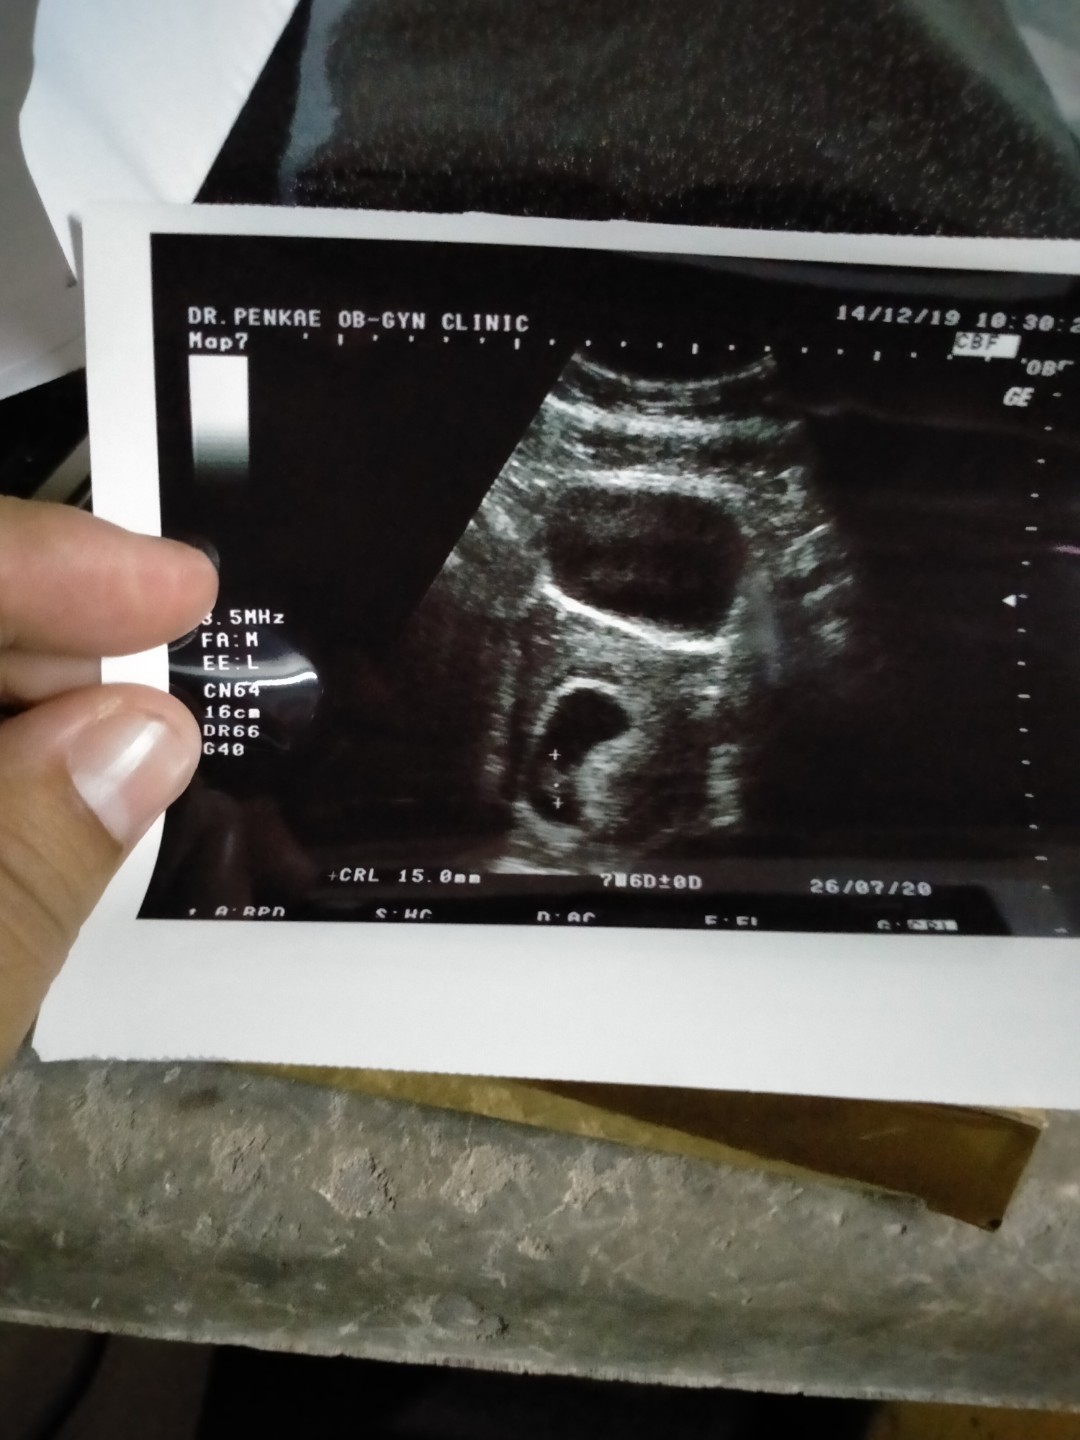

ซาวตอน9weekค่ะ